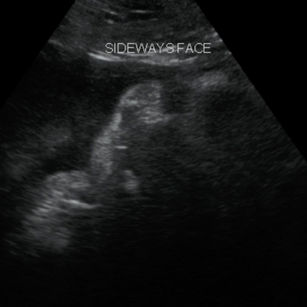

Position

Many babies are already head down by now.